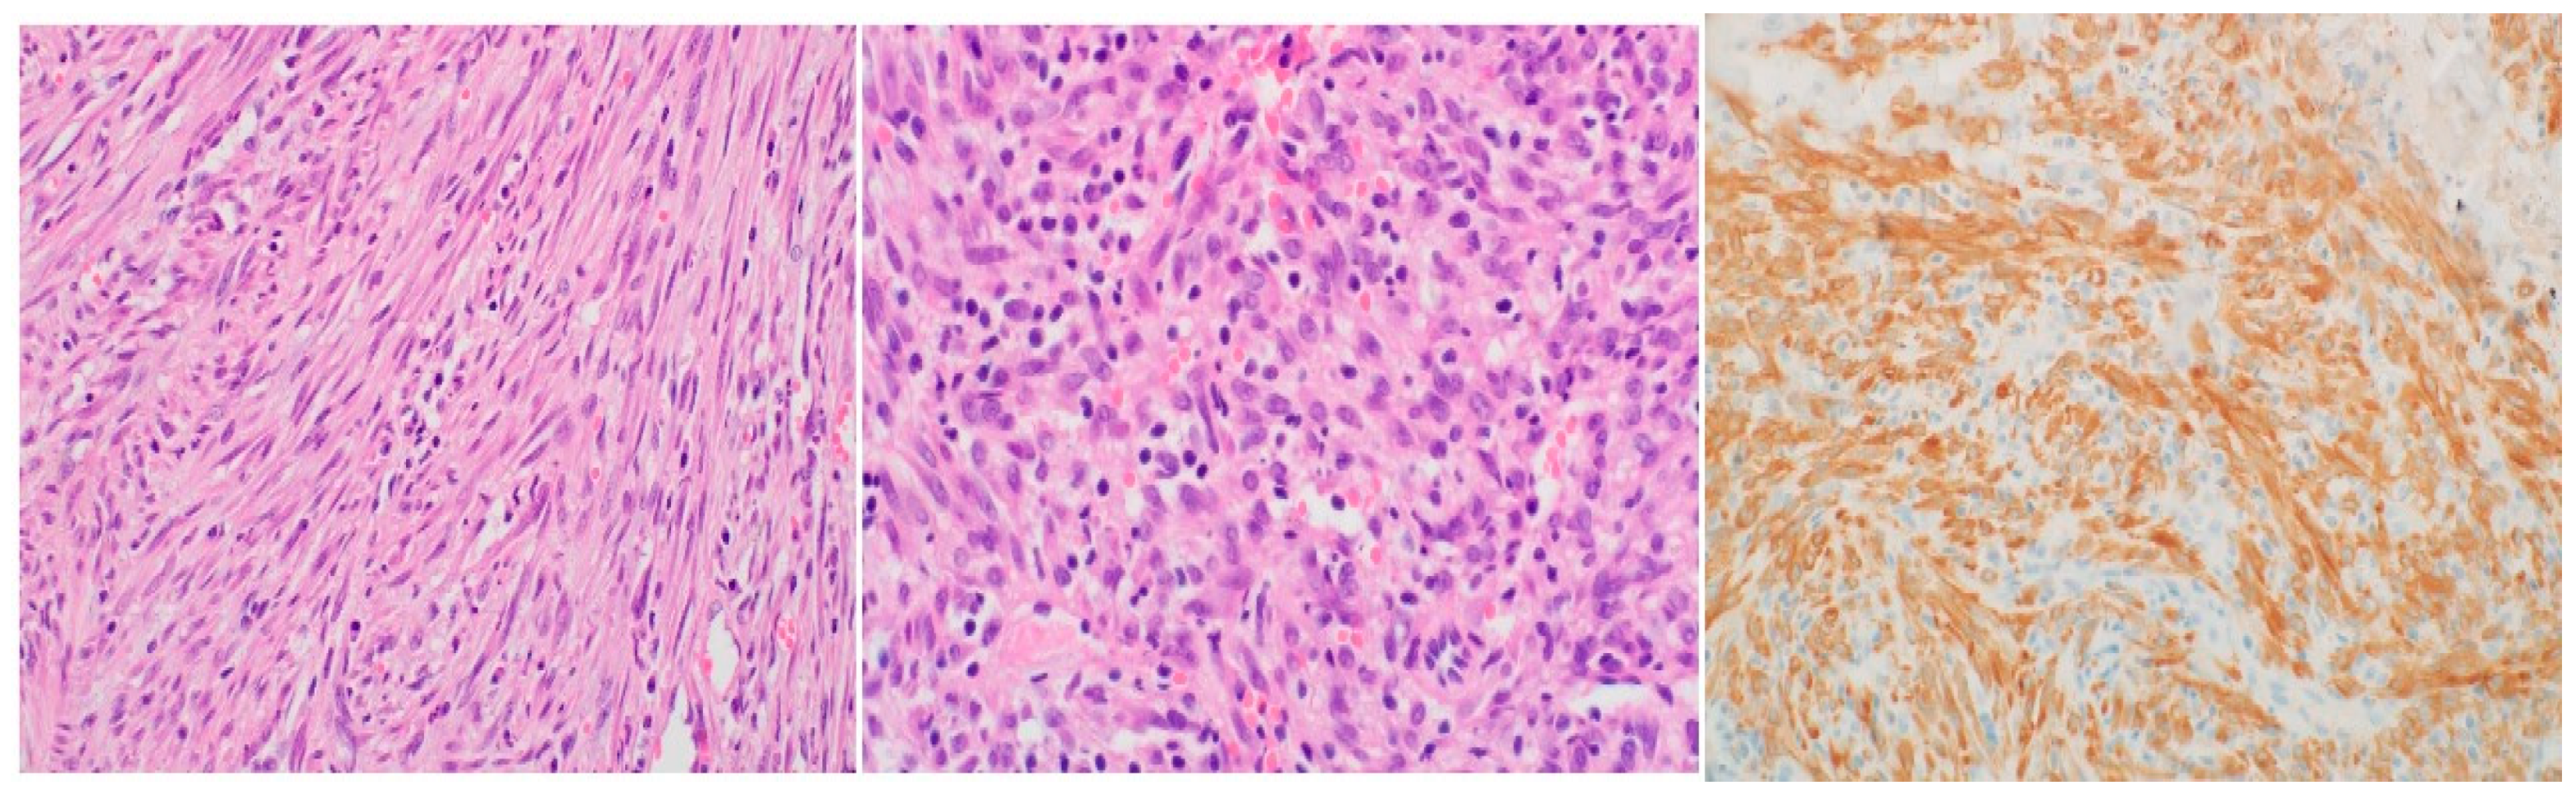

Histopathological analysis utilizing hematoxylin and eosin (H&E) staining exhibited a proliferation of spindle cells infiltrated by lymphocytes and plasma cells (Figure 2). Immunohistochemistry further revealed neoplastic cells positive for ALK, focally positive smooth muscle actin (SMA), and negative CD34 and desmin, ultimately confirming the diagnosis of IMT based on the histological examination. Following a review of the histopathology from the primary hospital and validation of the IMT diagnosis by our lung pathologist, a decision was made to proceed with a re-resection of the tumor and revision of the right main bronchus stump that had been previously divided at the flush with the carina.

The etiology and pathogenesis of IMT remain unclear, although it is often linked to a post-inflammatory process [12]. Histopathologically, Coffin et al. described three distinct patterns: compact spindle cell, vascular/myxoid, and hypocellular fibrous patterns, with the spindle cell pattern predominating overall [2] and in our case . The diagnosis of IMT can be challenging based on a single biopsy, necessitating complete resection for definitive diagnosis [12].

Figure 2. Histopathological findings: (a) Proliferation of bland spindle cells in vague fascicles. Nuclei show dispersed chromatin and compact nucleoli with rare mitotic activity; (b) Admixed intralesional inflammatory cells including lymphocytes and plasma cells; (c) Diffuse immunoreactivity is present for ALK-1 protein.